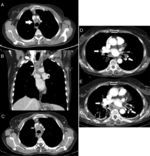

(A) Computed tomography image with contrast showing a pretracheal retrocaval mediastinal adenopathy with well-delimited necrotic center (white arrow). (B) and (C) Computed tomography images with contrast in coronal and axial planes showing mediastinal collections at left paratracheal (black arrow) and necrotic 2R adenopathy (white arrows) with thick wall enhancing. (D) Computed contrast tomography image showing small hilar (white arrows) and subcarinal (black arrows) adenopathies with punctate calcifications. (E) Contrast computed tomography image several days after EBUS, showing subcarinal liquid collection with peripheral enhancement (arrows).

A 42-year-old woman diagnosed with a grade 3 breast infiltrating ductal carcinoma (stage cT2N+), was initially treated with neoadjuvant chemotherapy, left mastectomy, and monthly trastuzumab. Recurrence was confirmed through biopsy of a solitary pulmonary nodule. Later on, a chest CT revealed a well-delimited and necrotic pretracheal mediastinal adenopathy (2R) (Fig. 1A), which was biopsied by EBUS-TBNA under sedation (midazolam, 6mg; Olympus needle, 21-gauge) and a total of 4 passes, without complications. Malignancy was confirmed. After 48h, she started feeling general malaise, retrosternal pain radiating to the neck, odynophagia, dysphagia, fever, and erythematous, and pruriginous maculo-papular lesions in the trunk and upper limbs. In blood analysis, we noticed a significant presence of leukocytosis and elevation of C-reactive protein. Chest CT showed increased attenuation of mediastinal fat, well-defined wall collections in the left upper and lower paratracheal space (Fig. 1B and C). Treatment response with ceftriaxone and clindamycin was good and did not require surgical debridement. Blood cultures and punctured adenopathy were negative. The evolution was favorable and after 11 days she was discharged, continuing treatment at home.

A 74-year-old woman was monitored in Pulmonology Clinic for presenting mediastinal lymphadenopathy (Fig. 1D). EUS-FNA (Cook needle, 22-gauge) was performed with a total of 4 passes (subcarinal adenopathy, 7), with no immediate complications. Tuberculosis was confirmed in anatomopathological samples. The next day she started having retrosternal pain not associated with any other symptomatology. After two weeks, she went to Emergency because of persistent pain and fever. As she was hemodynamically unstable she was admitted to the Intensive Care Unit. Blood tests revealed leukocytosis and hyperfibrinogenemia. The chest CT showed three well-defined liquid collections of adjacent fat (Fig. 1E). Right-assisted videothoracoscopic surgery drained the collections and a mediastinal lavage was performed. Cultures of the purulent material obtained during surgery were positive for Streptococcus spp, Pasteurella multocida and Peptostreptococcus. Antibiotic treatment was completed with ceftriaxone, vancomycin and clindamycin with positive effect. After a month of admission, she was discharged without further complications.